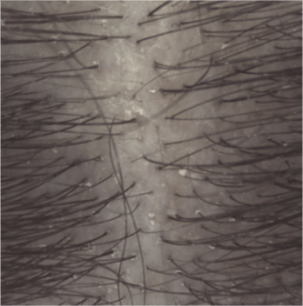

Efficacy results

Induration at 1 month (3).

(1) Clinical study on 54 subjects with light to moderate psoriasis on the scalp. 4 week attack phase: 3 shampoos per week

(3) Clinical assessment of plaque induration at D29.